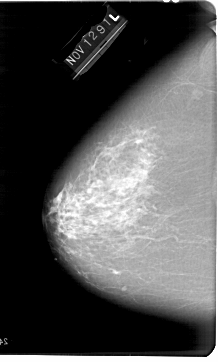

A_1648_1.LEFT_MLO

LEFT_MLO LINES 6481 PIXELS_PER_LINE 4201 BITS_PER_PIXEL 12 RESOLUTION 43.5 NON_OVERLAY